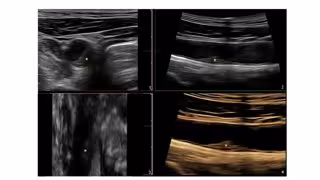

Además, el director de Investigación Clínica del CNIC, Borja Dr. Ibáñez, ha comentado que gracias a estas técnicas de imagen, especialmente las más sencillas, accesibles y que no necesitan radiación, como la ecografía vascular 2D y 3D, se puede detectar y cuantificar la carga o el volumen de enfermedad aterosclerótica y monitorizarla de una forma "precisa" para identificar a aquellos individuos que se puedan beneficiar potencialmente de una prevención más intensiva de forma precoz.

"La técnica recomendada es el TAC de baja dosis de radiación, que evalúa la presencia de calcio en las arterias coronarias como dato indirecto de la presencia de placas de aterosclerosis. Pero, además, las guías también ponen en valor la utilidad de la evaluación de la carga de aterosclerosis carotidea y femoral mediante la ecografía", ha añadido Ibáñez.

En concreto, lo que ahora aporta el estudio es un seguimiento a tres años del estudio 'PESA' en el que se ha llevado a cabo la primera comparación directa entre ambos marcadores de riesgo en imagen, el calcio coronario por TAC y la carga de aterosclerosis carotidea y femoral por ecografía 2D/3D.

"Y los resultados muestran que la ecografía de las arterias periféricas es capaz de detectar la progresión de la aterosclerosis de una forma más eficiente que el estudio del calcio coronario por TAC", ha apostillado la autora principal del artículo, Beatriz López-Melgar.